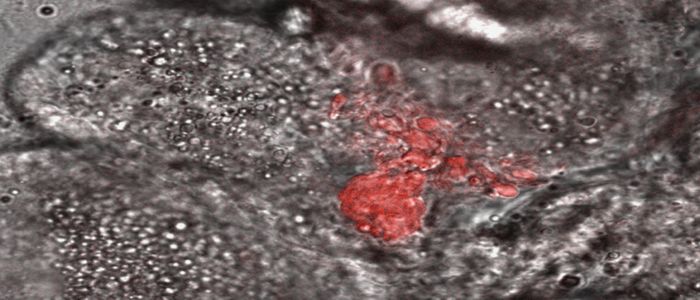

Research on brain swelling in children with cerebral malaria reveals potential new treatment approach